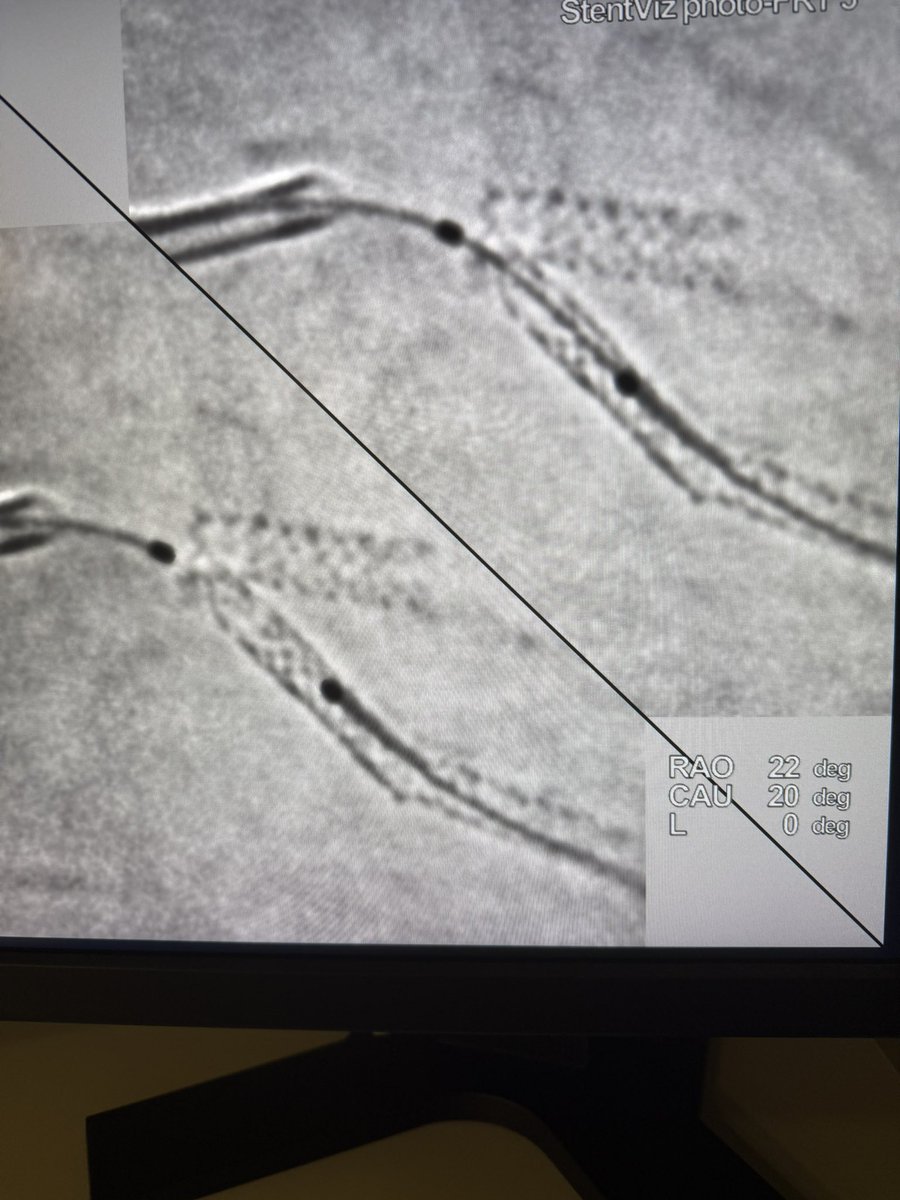

#CTO #HDR #MAT #MHA #singleaccess #EuroCTO #EUROACTOS2025 Live CTO CASE. RCA CTO How to do #HDR . Pilot 200→HDR→sionblack→HDR→sionblack→HDR→sionblack→CB+Stent+DCB @realarainmd @cto_chip_japan @DaitaroK @calcbreaker @UmihikoKaneko @SKuramitsu0511 @tadano98 @rotamonster

7

9

56